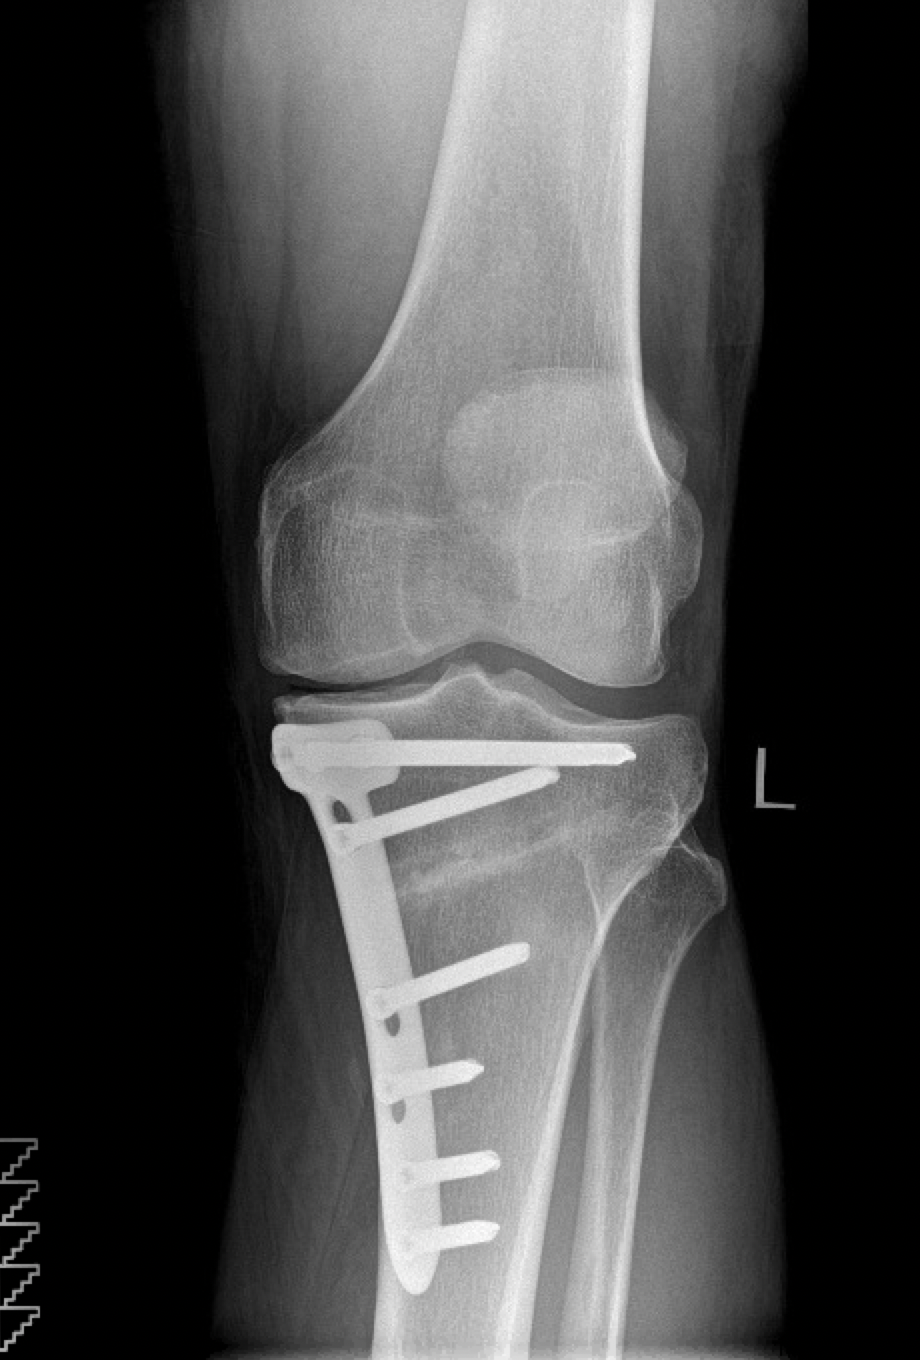

HIGH TIBIAL OSTEOTOMY

I am now more active than I have been in many years

I had High Tibial Osteotomy surgery with Mr Mihai Vioreanu in November 2016. Having osteoarthritis in my left knee left me unable to enjoy a normal active life without pain if I spent long periods walking or standing.

Read more

"Enjoying an active life"

I had High Tibial Osteotomy surgery with Mr Mihai Vioreanu in February 2015. I had been in terrible pain with my knee in 2014 following arthroscopic 'clean-out' performed in a different hospital. Mr Vioreanu was excellent during all my consultations with him. He spoke openly and plainly about the surgical procedure in layman's terms. He thoroughly discussed all the pros and cons involved. Mihai was always ready and available to assist me after surgery. I am now back to a normal lifestyle and en

"Best decision I made"

I decided to go for it and can honestly say it was one of the best decisions I made. 6 months later and I'm walking and hiking pain free, performing all manner of exercise and am working towards running/jogging.

BILATERAL HIGH TIBIAL OSTEOTOMY

"Mihai professionalism and experience is top class"

Mihai put a plan in place over three years to carry out surgery on both legs. The surgeries were a great success.